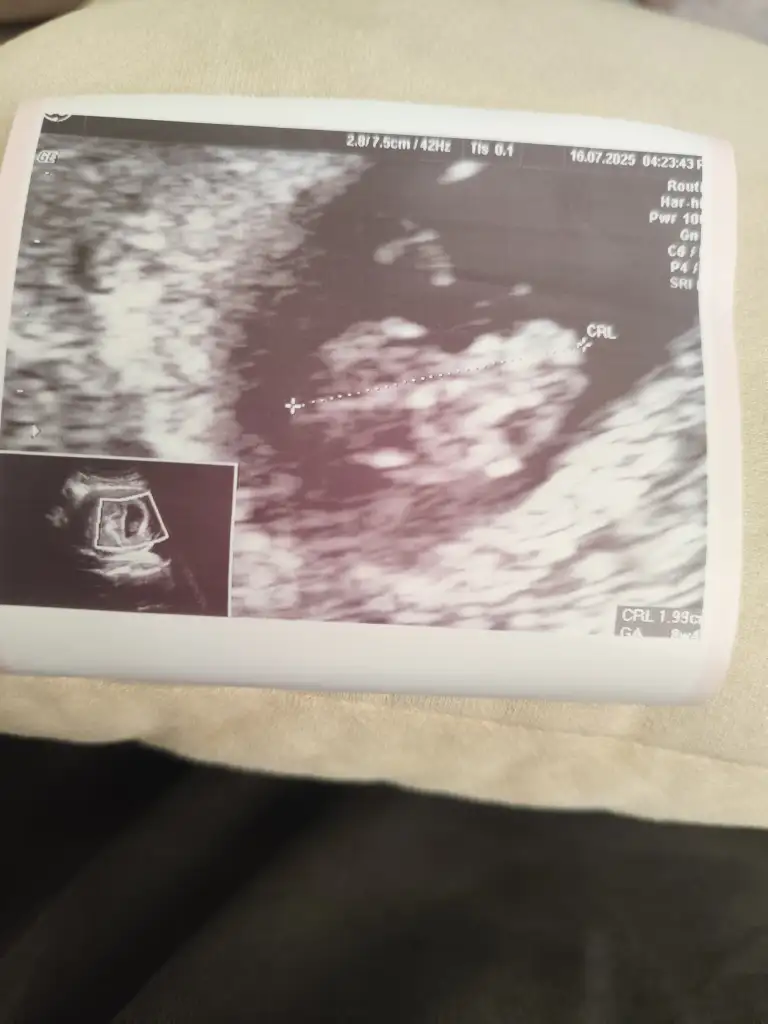

Muhtemelen kız6 haftalık vajinal ultrason görüntüsü bize de bakabilir misiniz lütfen, teşekkür ediyorum şimdiden

KızSelam , sizce nub teorisine gore benimki ne

Merhaba nubu düz kız olabilirSelam , sizce nub teorisine gore benimki ne

Burda 8.4 bugün tekrar gittim onu aticaktimSizin bebeğinizin görüntüsü değilmi

Tamam işte kıza benziyorBuda 9+4